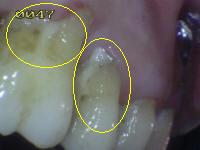

Debe eliminar la placa bacteriana de las

superficies (UCE) unión cemento-esmalte por

medio del cepillado mecánico o cepillo dental, para poder observar áreas de

desmineralización si las hubiere. Ver

círculos en amarillo.